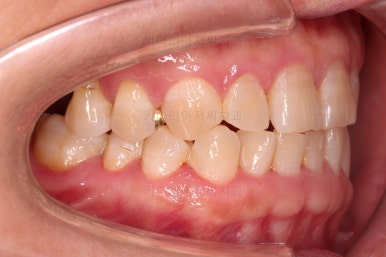

전후사진을 비교해보겠습니다.

쓰러진 치아도 원위치로 만들어 기능을 회복시켜주었고, 임플란트도 1개로 마무리를 할 수 있었어요.

이렇게 단순히 임플란트를 해야지 하는 상황도 간단한 교정치료와 병행한다면 치아도 아끼고 임플란트도 줄이는 매우 좋은 부산교정치료 될 수 있답니다.